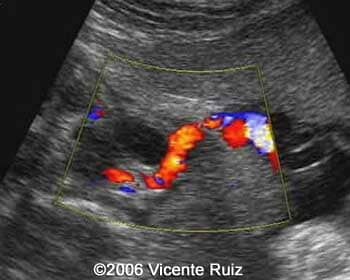

Single umbilical artery